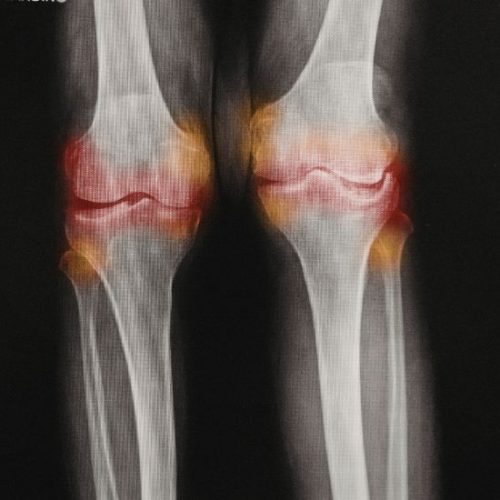

La gonartrosis, comúnmente conocida como osteoartritis de la rodilla, es una afección degenerativa de las articulaciones que afecta a un número significativo de...